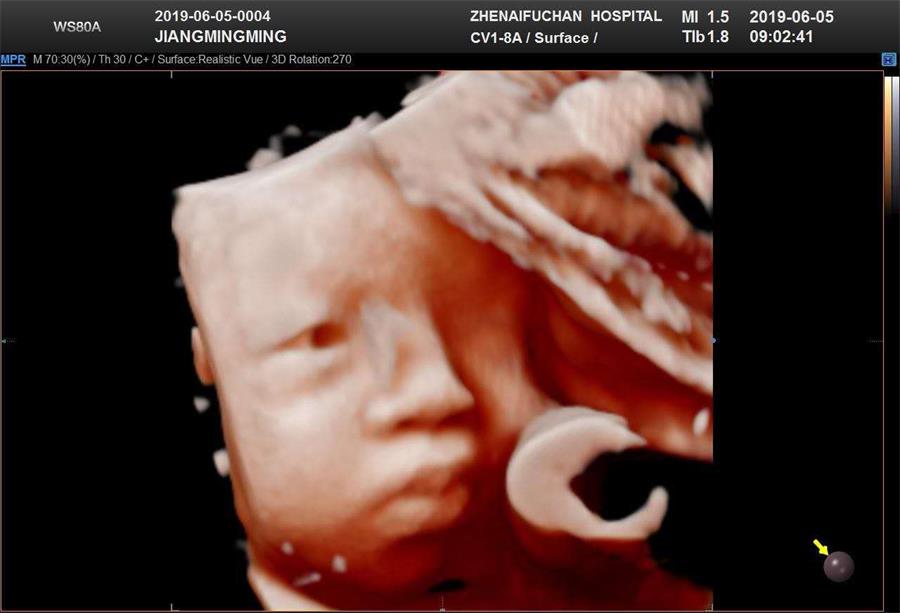

5D彩超,顾名思义,5D是“五维”的缩写。它就是采用4D超声图像加上空间维度参数,获取更加立体、逼真的五维图像。五维(5D)彩超具有极高的清晰度及分辨率,能360°立体呈现胎儿宫内发育情况。比大家所熟知的四维彩超清晰度更高,诊断范围更全面。能够更多方位、多角度的观察宫内胎儿的生长发育情况。在检查的同时,宝爸宝妈们还可以像观赏电影那样,看到TA乖巧的模样及一举一动。多方位、多角度地观察宝宝的生长发育情况,同时还能对孕妈妈的健康进行检测。

其优点是:能够栩栩如生的显示您未出生的宝宝在妈妈肚子里的实时动态活动高仿真图像。